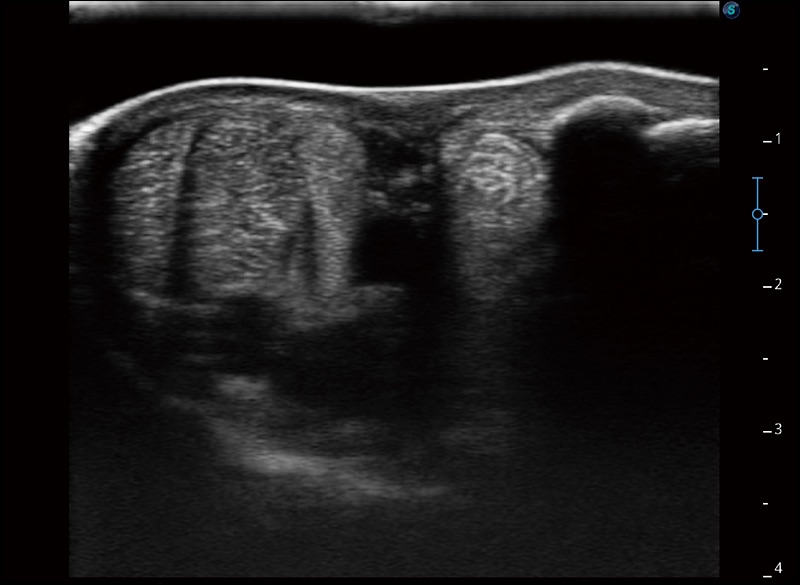

α1卓越的图像质量和便捷的工作流程,使每位宠物医生都能轻松扫查。其全面的兽用应用功能和紧凑型的结构设计,可以满足动物检查的多种需要。专业的预设检查模式和多领域测量软件包有助于为不同类型的动物提供检查, 让宠物医生能够出色的完成工作。

任意波束合成技术

在不牺牲时间分辨率的情况下提供出色的图像

空间复合成像

优化不同角度的图像